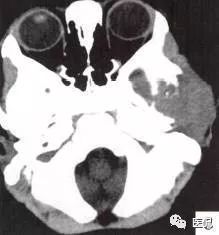

颅脑CT示:图A〜D,CT平扫示左侧额骨、蝶骨见溶骨性骨质缺损,边界清晰,周围无硬化边,伴有软组织肿块向脑外生长,边缘光滑,脑内无明显侵犯;

图E、F,横、 矢状位CT增强示软组织肿块轻度均匀强化,两病灶间亦见强化软组织影;

2.定位诊断:额骨、蝶骨均可见局限性骨质破坏,穿破颅骨内外板,见软组织肿块突向脑外;肿块与硬脑膜界限清楚,脑实质无侵犯;应考虑颅骨来源,向颅外侵犯。

②颅骨多处溶骨性破坏,穿透颅骨内外板;

③骨破坏无 硬化边,边缘光整,无膨胀;

④软组织肿块形态规则,边缘光滑;⑤脑膜及脑组织无侵犯, 表现为推压或移位。后三点均支持为良性肿块,结合年龄、实验室检查等,诊断不难。本例经病理(图I)证实为:嗜酸性肉芽肿。